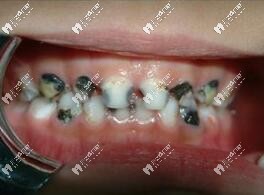

兒童齲齒圖片

兒童應(yīng)該3歲開始看牙,在這期間如果不重視,孩子有齲齒不及時(shí)發(fā)現(xiàn),會(huì)導(dǎo)致孩子牙痛難忍,換牙期(6 歲一12歲)更要定期到醫(yī)院檢查牙齒,因?yàn)榭赡軙?huì)出現(xiàn)換牙時(shí)間、順序不對(duì),牙齒長(zhǎng)得不整齊, 所以定期請(qǐng)兒童口腔醫(yī)生檢查是必要的。